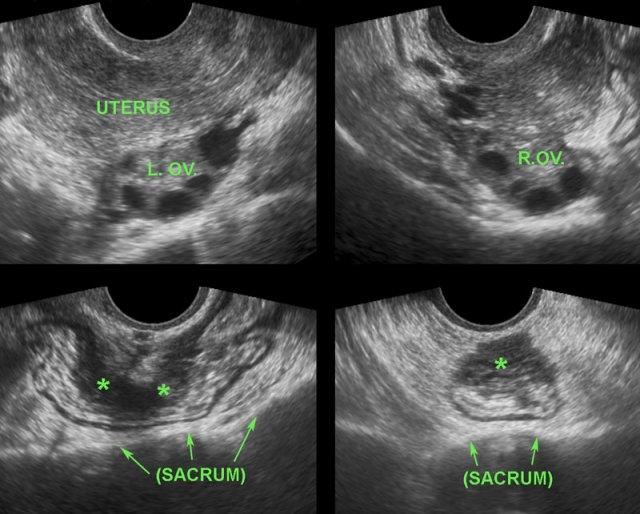

Các hình ảnh thuộc về một bệnh nhân DIE với hình thái tử cung và buồng trứng bình thường.

DIE có các đặc điểm TVUS điển hình, gần như đặc trưng bệnh lý.

Mặc dù rõ ràng là một bệnh lý phụ khoa, nhưng không hiếm trường hợp bị các bác sĩ phụ khoa bỏ sót trong quá trình thực hiện TVUS.

Lý do là phần lớn bệnh nhân DIE (*) không có các nang lạc nội mạc tử cung điển hình và, như ở bệnh nhân này, có tử cung và buồng trứng bình thường (buồng trứng trái và buồng trứng phải). Hơn nữa, chẩn đoán TVUS của DIE đòi hỏi kiến thức chuyên sâu về hình ảnh siêu âm của ruột và bàng quang bình thường cũng như bệnh lý, kiến thức này có thể còn thiếu ở các bác sĩ phụ khoa.

Các ổ lạc nội mạc tử cung trên bề mặt ngoài của đại tràng ở bốn bệnh nhân khác nhau.

Các ổ lạc nội mạc tử cung (*) trong túi cùng Douglas là các khối đặc, giảm âm, kém mạch máu, khu trú không đối xứng, liên tục với lớp cơ giảm âm phía ngoài của đại tràng.

Lớp dưới niêm mạc tăng âm phía trên và niêm mạc đại tràng thường còn nguyên vẹn. Điều này cũng giải thích tại sao máu trong phân khá hiếm gặp trong DIE.

Bờ ngoài của các khối giảm âm này thường dính chặt vào tử cung và/hoặc cổ tử cung. Thường có thể thấy hình ảnh tua gai hoặc “kéo căng” ở các bờ ngoài.